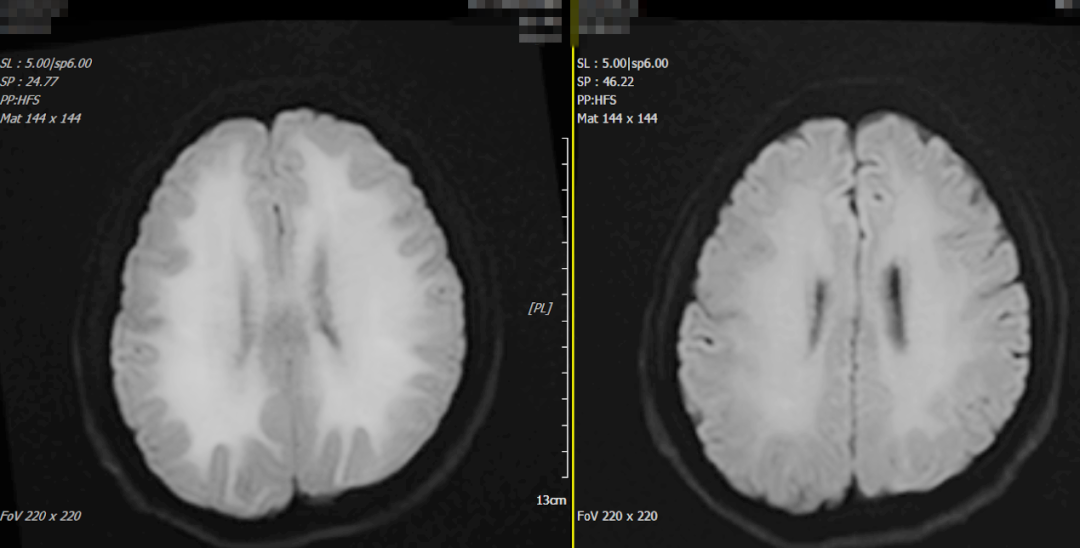

2月22日颅脑MRI 5月21日复查颅脑MRI

21日开始,郭阿姨病情迅速恶化,出现肢体震颤、四肢瘫痪、混合性失语、吞咽困难、高热及昏迷等症状,住院期间合并肺部感染、应激性上消化道出血、下肢静脉血栓形成等并发症,予留置胃管、肠内营养支持、亚低温脑保护、抗感染、护胃、高压氧等治疗。因患者病情危重,28日神经内科邀请我院客座教授、广东省人民医院神经内科何池忠副教授会诊,何池忠副教授查看患者及详细询问病史,结合患者相关辅助检查,考虑一氧化碳中毒迟发性脑病可能性大,因患者病情进展快,病情危重,双侧侧脑室旁脱髓鞘面积大,不排除中毒后诱发免疫性疾病,患者目前广泛大脑皮层损伤症状,治疗难度大,预后差。根据会诊意见,神经内科完善腰椎穿刺术及脑脊液相关检查,继续予亚低温脑保护、脱水降颅压、丙种球蛋白冲击等治疗。